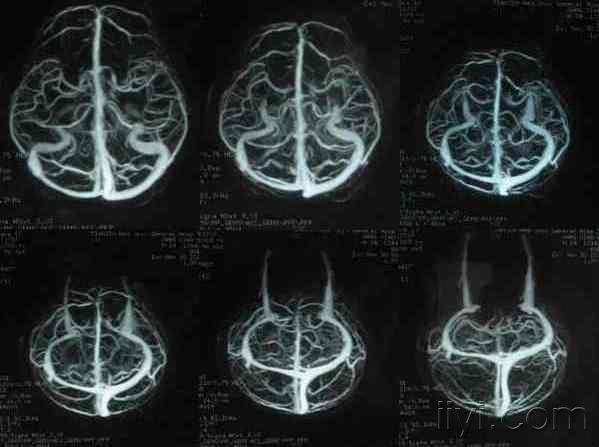

大脑的静脉系统mrv

绝对干货6张图完美解释大脑静脉系统mrv及各自引流区域

硬货收藏6张图完美解释大脑静脉系统mrv及各自引流区域

短小精悍6张图完美解释大脑静脉系统mrv及各自引流区域

剪除了深静脉系统的mrv由大脑半球引流至上矢状窦的静脉:1,额极静脉2